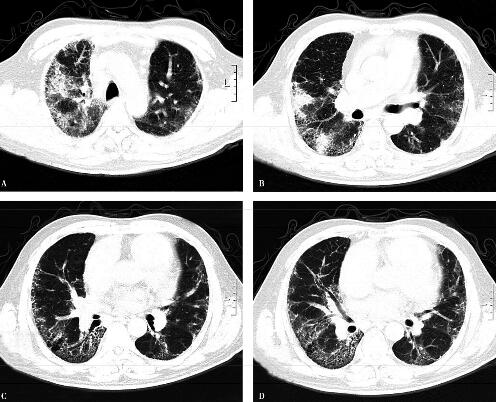

4.胸部CT:

双肺野弥漫性索条状,斑片状阴影及磨玻璃影,近胸膜处可见纤维网格影,以双下肺为著。心包积液,双侧胸膜增厚(图1)。

图1